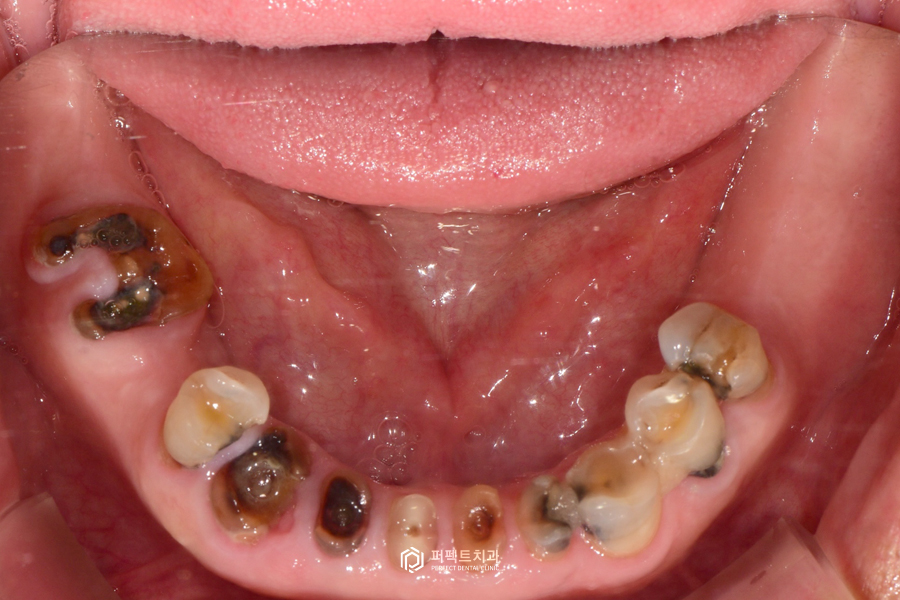

초진 구강사진

실제 구강 내 사진을 보시면 없는 치아들이 많고, 남아있는 치아도 모두 썩어있는 것을 보실 수 있습니다. 그리고 중요한 점은 치아가 계속 없이 지내게 되면 치아가 닳고 썩어서 교합이 무너진 상태입니다.

무너졌다는 것은 원래 씹는 높이가 정상이었는데 닳고 부러지면서 교합이 낮아져 있는 경우입니다. 이렇게 낮아진 교합 높이를 올리는 수복까지 다같이 이루어져야 해서 난이도가 높은 케이스에 해당하는 경우입니다. 이런 경우는 어떻게 해야 되냐면 임시치아 혹은 임시틀니를 이용해서 그 높이를 맞춘 다음에 거기에 맞는 최종보철을 만든 그런 경우라고 보시면 될 것 같습니다.